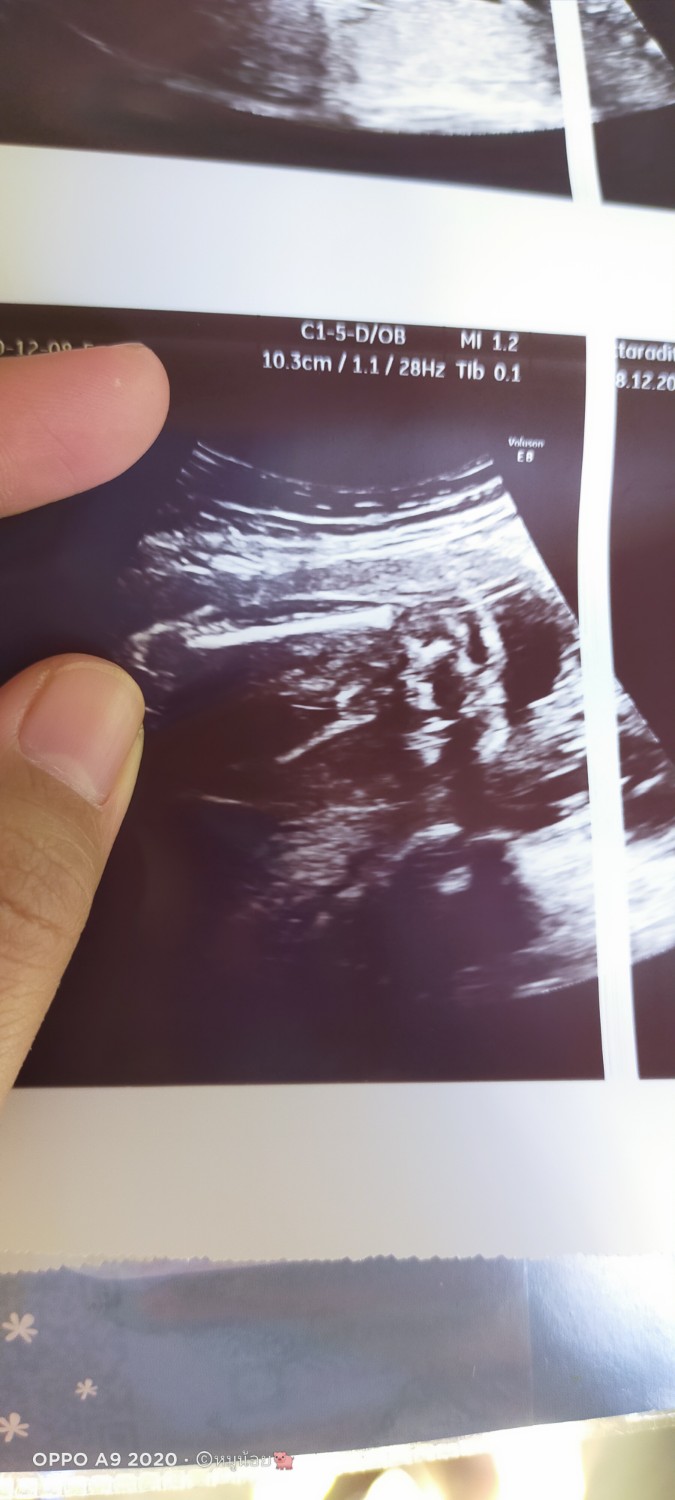

ช่วยดูหน่อยค่ะหมอบอกได้ลูกสาว ดูไม่ออกค่ะช่วยดูหน่อยค่ะ

มีลูกชายแล้ว2คนค่ะแต่ชาวด์ไม่เคยชาวด์เห็นเลยทั้ง2คน มาคนนี้หลุดยาฉีดมา ขอหมอชาวหมอชาวให้ หมอบอกว่าได้ลูกสาว พร้อมหันจอมาให้ดู

แต่พอปริ้นมาคือดูไม่ค่อยเป็นช่วยดูหน่อยค่ะ